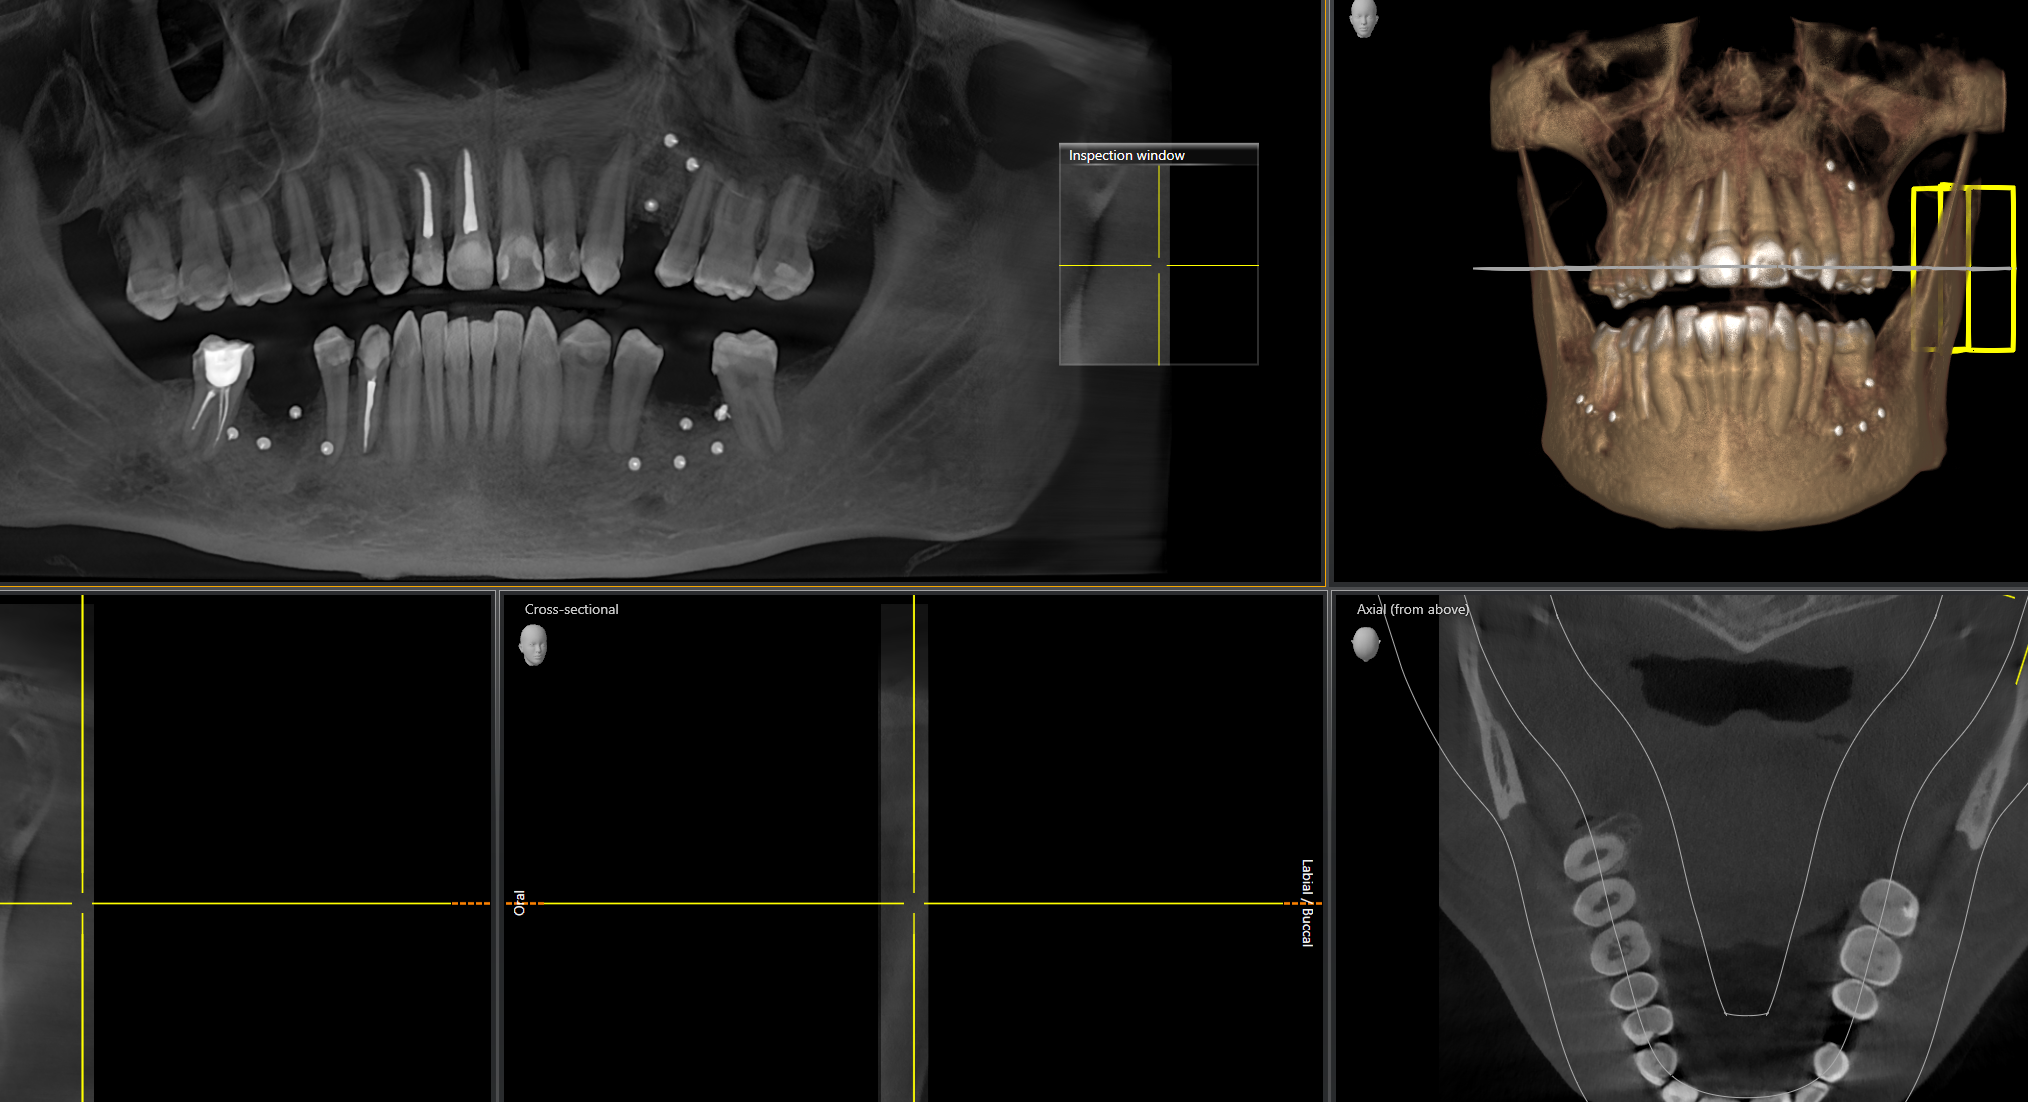

Ну и рекомендую сделать клкт, если не пригодится в этот раз, по крайней мере будет у тебя "паспорт" твоих зубов и каналов цена в пикассо около 3к.

Кстати, если мне выдали результаты КТ челюстей на диске, я могу с этим прийти в какую-то другую клинику за альтернативным мнением, или у всех свои форматы?

(на диске некий Planmeca Romexis Viewer - Romexis_Viewer_Win.exe для винды, Romexis_Viewer_OS_X.app - и папка data с результатами скана)